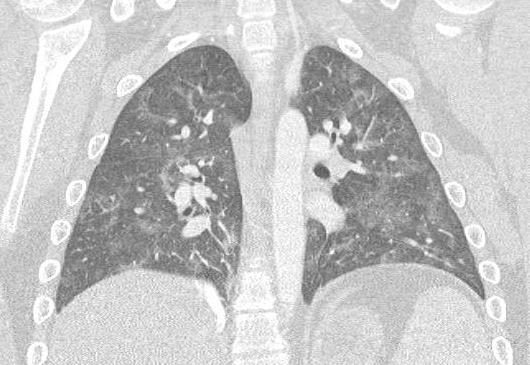

Acute Pediatric COVID-19: CT

21 Imaging of Covid 19 infection in children

3 Phases

Early: "Halo" sign

Local infection

Progressive: Diffuse GGO

Developed: Consolidation

Surr vasc congestion

Inflammation - adj alveoli

Alveoli fill with fluid/cells

CT

• Bilateral & multifocal GGO, +/Consolidations or both

• Halo sign

• Peripheral and subpleural